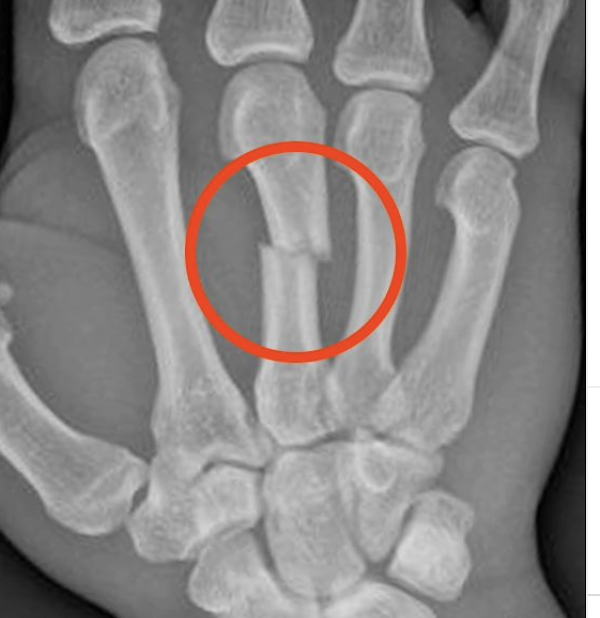

骨折した右拳(@jeansilvamma)